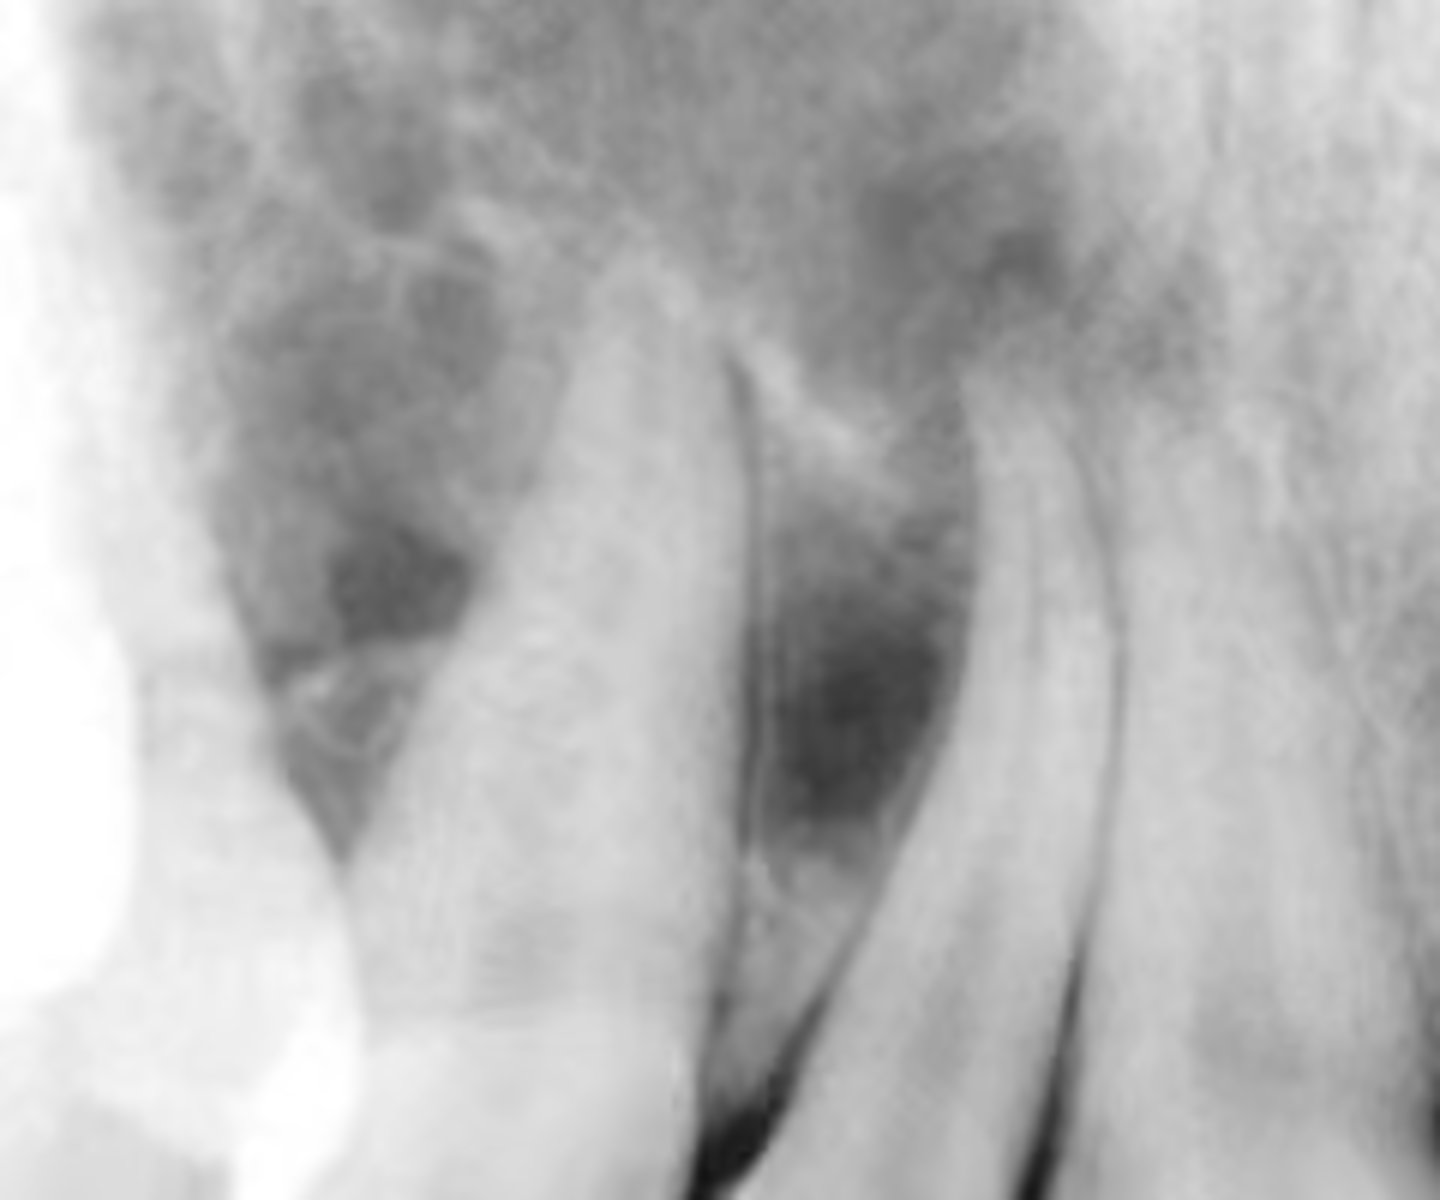

how would you describe the lesion?

A. well-defined, non corticated, periapical radiolucency associated with tooth number 14

B. ill-defined, non corticated, periapical radiolucency associated with tooth number 14

C. well-defined, corticated, pericoronal lesion with radiopaque flecks associated with an impacted tooth

D. well-defined, corticated, pericoronal radiopacity associated with an impacted tooth

What category would you put this lesion into?

Benign odontogenic tumor/cyst

all of the following could be a differential diagnosis for this lesion except?

A. AOT

B. calcifying epithelial odontogenic tumor (pindborg tumor)

C. Calcifying Epithelial odontogenic cyst (gorlin cyst)

D. osteosarcoma